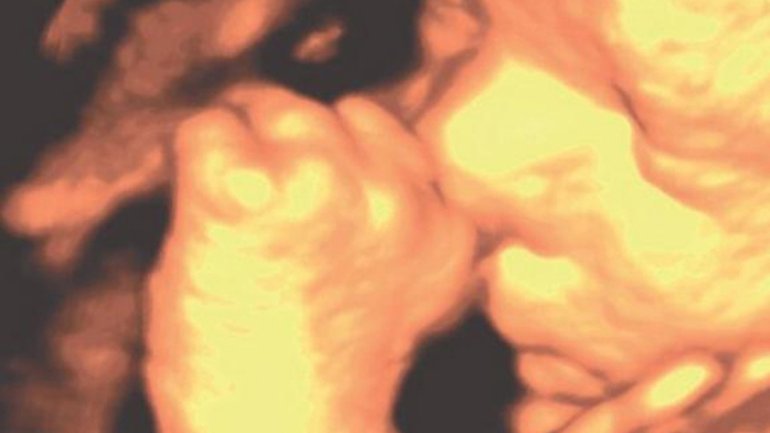

Ultraschall 30. SSW

Der 3-D-Ultraschall zeigt das Gesicht des Babys und die beiden kleinen Hände. Etwa in der 30. Schwangerschaftswoche nehmen Babys die Fötusstellung ein, indem sie aus Platzmangel die Beine anziehen und die Arme vor dem Körper verschränken. Letzteres ist auf diesem Bild zu erkennen.